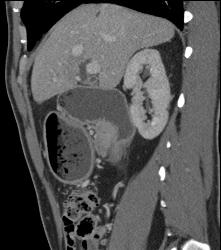

GIST Tumor